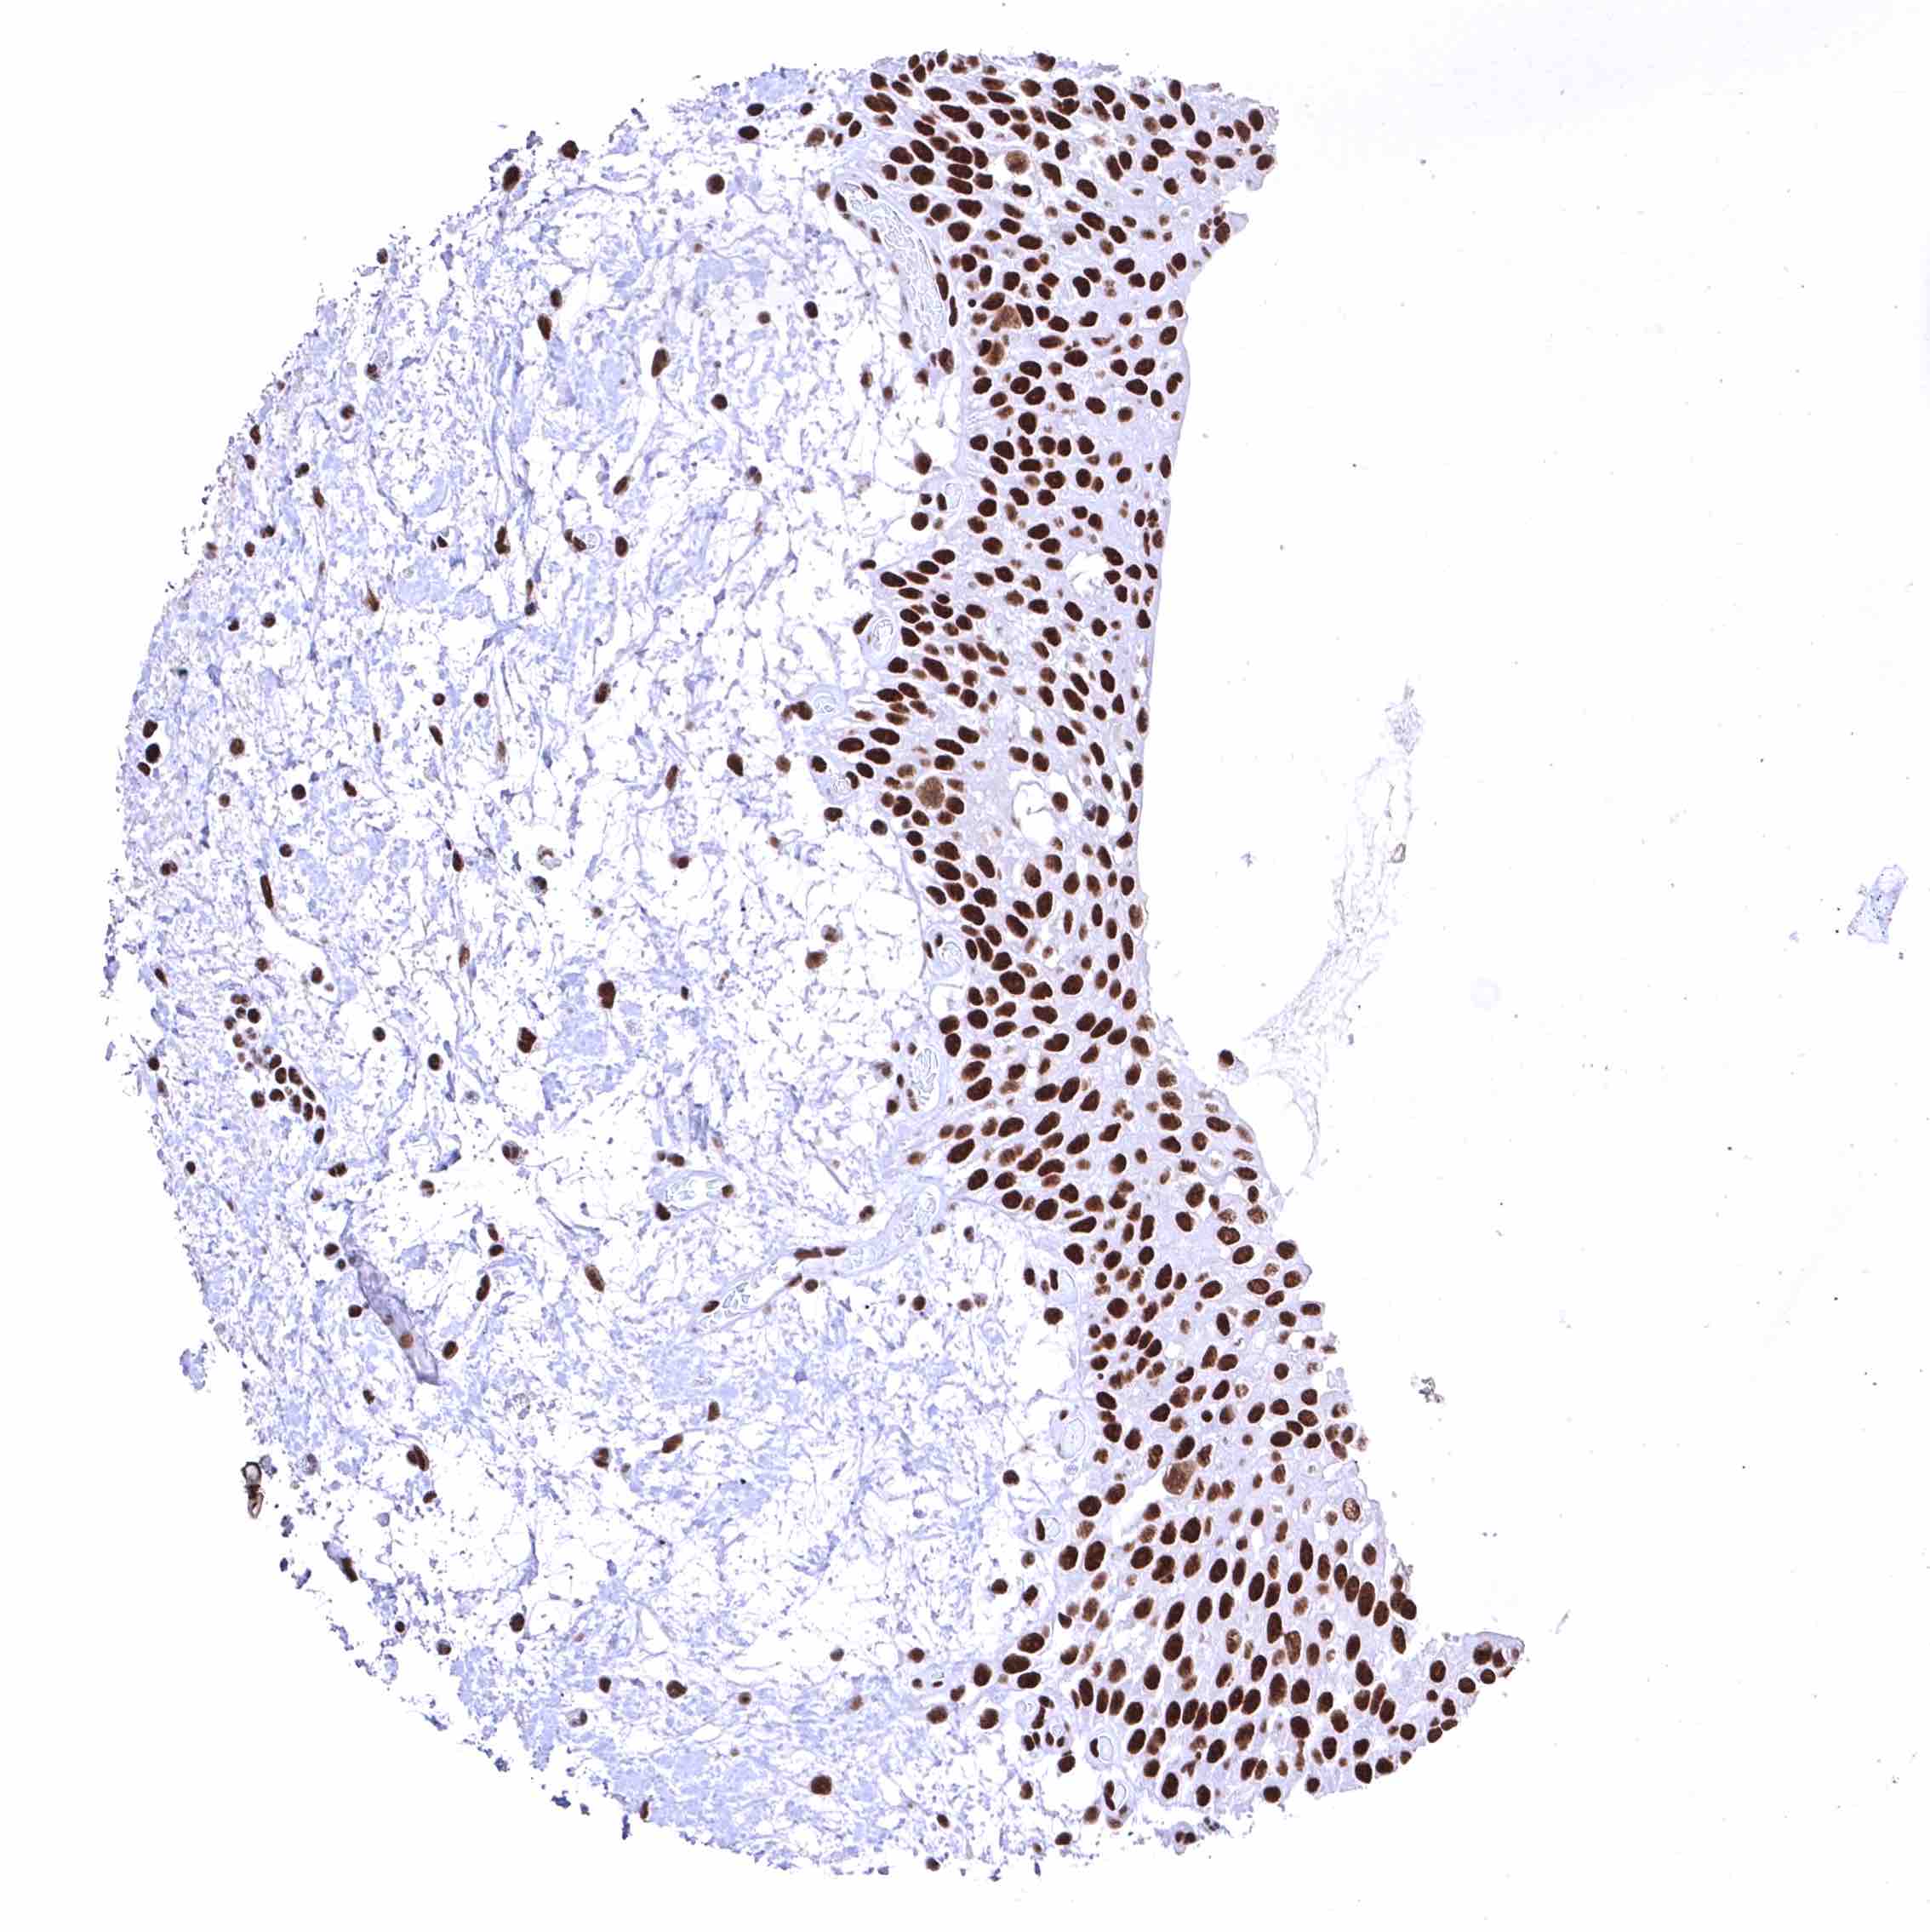

Uterus, ectocervix – Distinct nuclear BRD4 staining of squamous epithelial cells with a slight decrease of the staining intensity towards the most superficial cell layers.